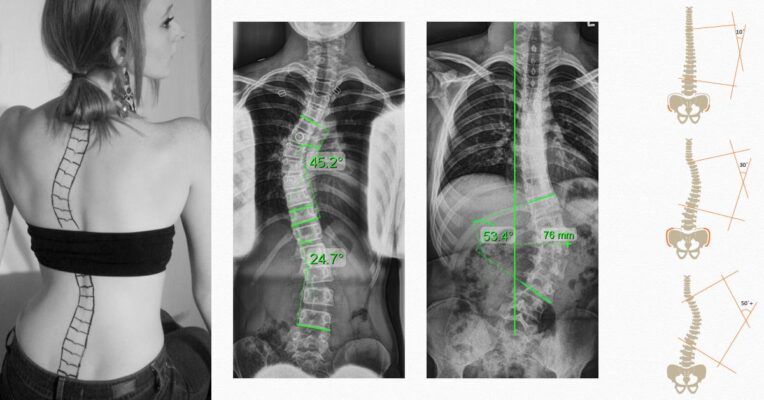

Graus de gravidade da escoliose: Compreender a classificação e o tratamento

Scoliosis is a complex spinal deformity that affects millions worldwide. This study aims to classify [...]